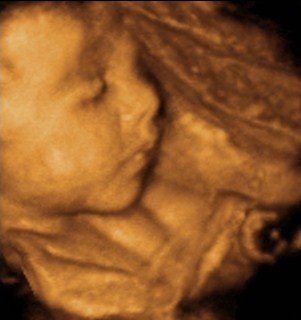

Sajnos visszaolvasni most még nem tudok, de feltétlenül fel akartam tenni Melcsi Marcika fotóját.

Ezt nézzétek meg. Annyira, de annyira édes kis pofija van!!!

Na csajok milyen a kincsem?

Már most látszik, hogy mennyire szép gyerek lesz!!! Mindig elcsodálkozom, hogy milyen fantasztikus az uh!!!